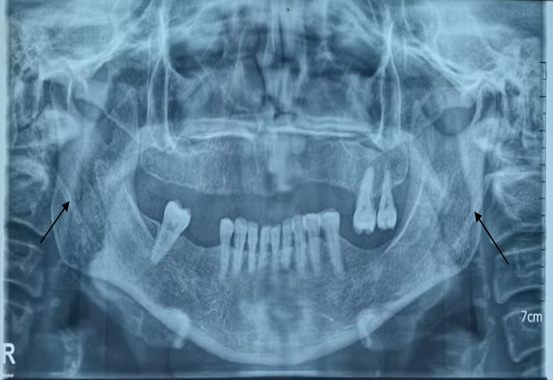

The orthopantomogram (Figure 1) revealed elongation of the styloid process as well as calcification of the bilateral stylohyoid ligament.

Figure 1: On the panoramic radiograph, the stylohyoid and thyrohyoid ligaments are clearly visible bilaterally, creating a superimposed image relative to the mandibular angle